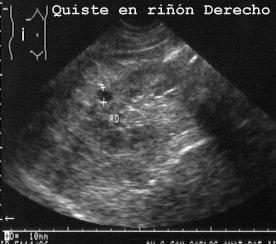

quistes renales (Fig 13),

13QUISTR.JPG (25418 bytes)

Fig 13

y un quiste esplénico. Todos ellos son estructuras pequeñas que quedaron ocultas en el interior de las secciones macroscópicas de los órganos correspondientes.